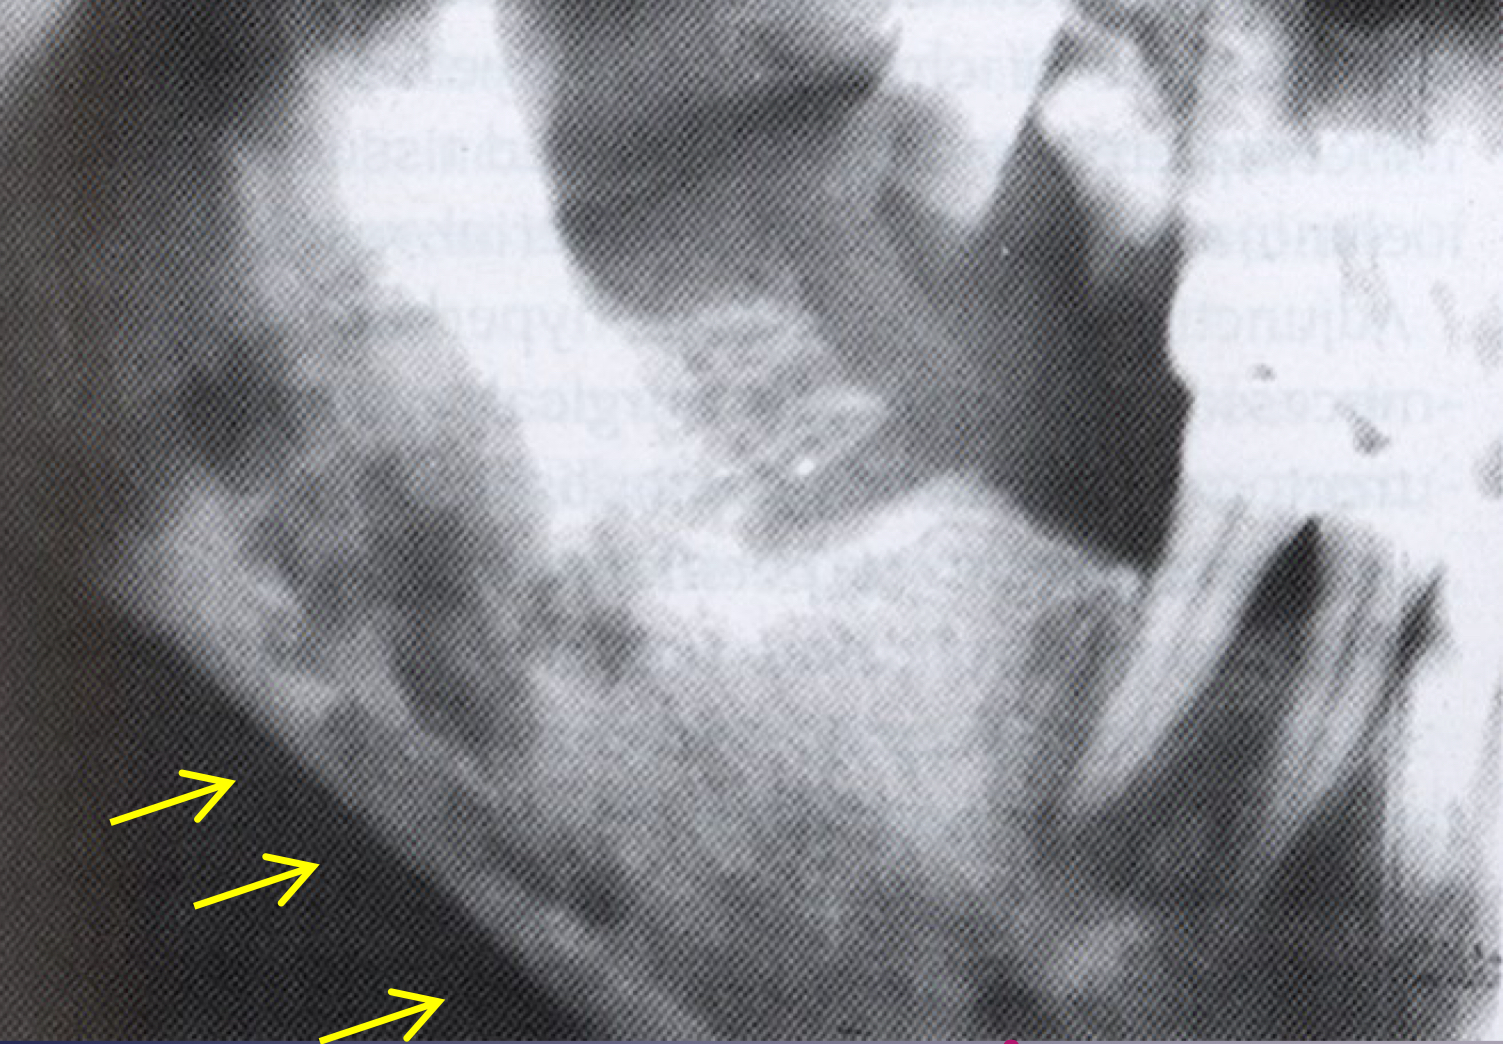

which osteomyelitis phase?

internal structure:

sequestration, sinus tract or fracture

acute

white and black arrow

which imaging is method of choice for seeing internal structure (sequestrea) of acute osteomyelitis?

CT/CBCT